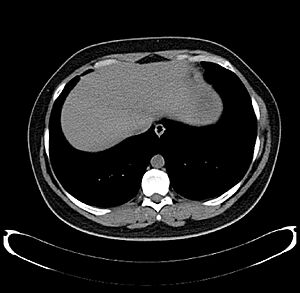

What the Liver Looks Like

The liver is a dark reddish-brown organ shaped like a wedge. It has two main parts, called lobes, which are different sizes. A human liver usually weighs about 1.5 kilograms (3.3 pounds) and is about 15 centimeters (6 inches) wide. Its size can vary a bit from person to person.

It sits in the upper right side of your belly, just under your diaphragm (the muscle that helps you breathe). It's also to the right of your stomach and on top of your gallbladder.